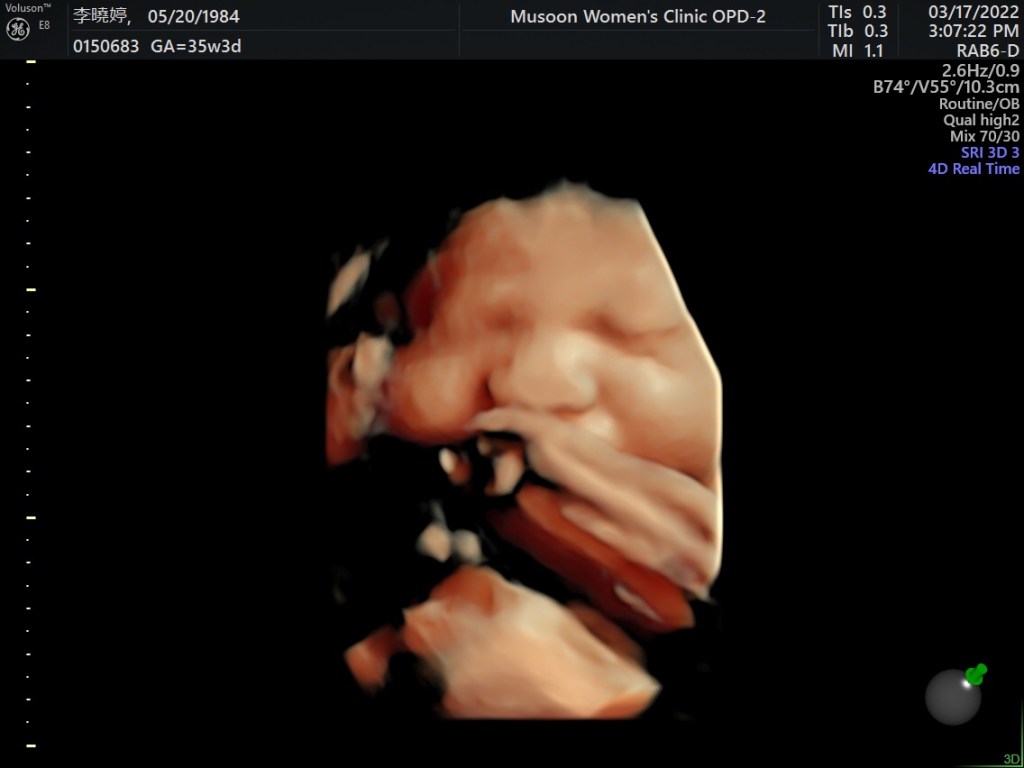

胖胖雲na,32週開始就肉肉的,常常因為哥哥的哭聲在媽媽的肚子裡動得更厲害。哥哥也會抱著媽媽的肚子拍拍(這時期的孩子都是用拍打的),但對肚臍更有興趣。